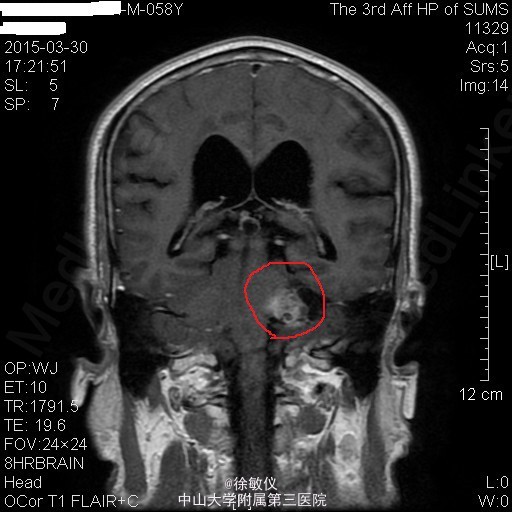

老年患者,主诉:左耳耳鸣、听力下降8年,伴头痛2个月。 现病史:患者8年前始无明显诱因反复出现左耳耳鸣,自诉如鞭炮样鸣响,伴听力进行性下降,无耳道流血流液,可自行缓解。患者曾至当地医院就诊,保守治疗后改善不明显。2个月前始患者出现阵发性全头痛,偶伴头晕、恶心,近2周呕吐胃内容物2次,无发热,无肢体活动异常等不适。于当地医院行头部CT,结果提示:左侧桥小脑角区占位性病变伴出血,听神经瘤(神经鞘瘤)可能性大。患者为进一步治疗来我院。

查体:左耳听力缺失,右耳听力正常。余查体无特殊。 辅查:头部MR:1、左侧桥小脑角区占位病变,考虑为听神经瘤并出血、囊变,病变与左侧听神经、椎动脉关系密切;2、颅脑MRA示脑动脉未见异常。 头部CT:双侧额顶枕叶、半卵圆中心、侧脑室周围、放射冠、基底节区及右侧岛叶多发密度灶,考虑缺血变性灶;颅脑CTA示肿瘤与左侧椎动脉关系密切。